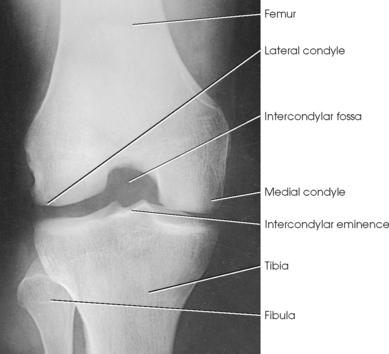

Structures shown: The resulting image shows an AP projection of the knee structures (Fig. 6-121).

Structures shown: The resulting image shows the joint spaces of the knees. Varus and valgus deformities can also be evaluated with this procedure (Fig. 6-128).